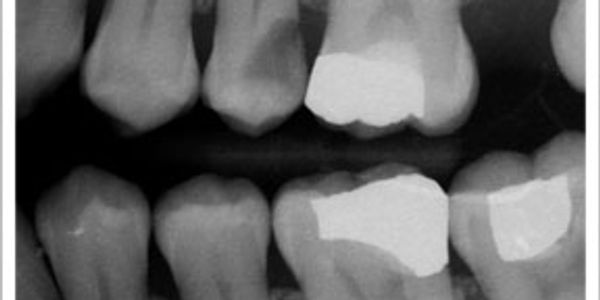

In the image provided, you can look at the upper pre-molar, notice the dark lesion present, that is a cavity. Your bitewing x-rays will show changes in the density of the enamel caused by bacterial infection. Once that infection has spread into the dentinal layer of your tooth, it's important to get it removed.